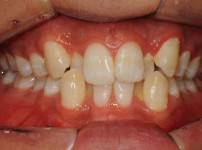

9

BEFORE

AFTER

클릭 해주세요.

앞니 벌어짐

치아교정